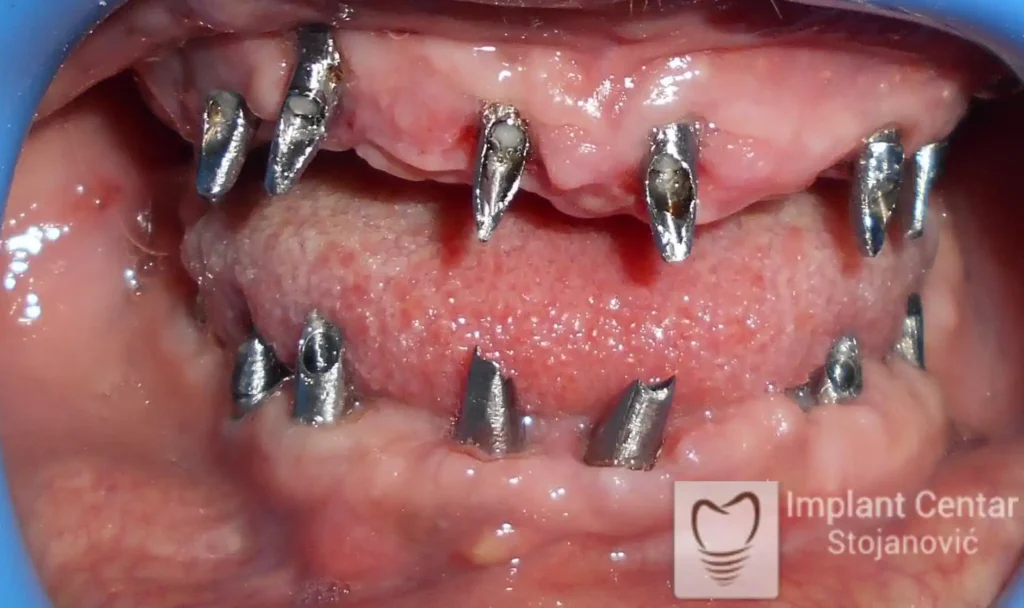

Pacijentkinja je došla sa dotrajalim mostovima i preostalim zubima loše biološke vrednosti, dok su bezubi prostori bili prisutni u gornjoj vilici sa desne strane i  u donjoj vilici sa leve strane. Nakon detaljnog kliničkog pregleda i analize snimaka, izvršeno je vađenje svih zuba i ugradnja optimalnog broja dentalnih implantata.

Već tri dana nakon operacije pacijentkinja je zbrinuta privremenim krunicama, kojima je bila oduševljena jer su odmah omogućile funkciju i estetiku. Nakon perioda oseointegracije izrađene su definitivne cirkonijum-keramičke krunice, čime je postignuta maksimalna estetika, funkcija i vraćeno samopouzdanje. Pacijentkinja je presrećna postignutim rezultatom.